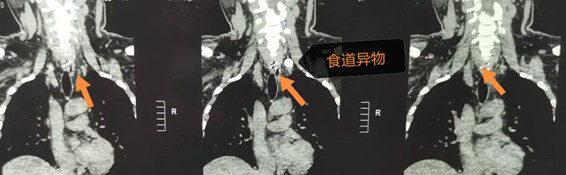

五官科主任李濤為患者詳細(xì)檢查后,推測異物可能在食道內(nèi),經(jīng)急診CT示:食道上段異物。

在李濤主任、李衛(wèi)征醫(yī)生及麻醉科、手術(shù)室的密切配合下,為患者施行了食道鏡探查+食道異物取出術(shù)。手術(shù)中發(fā)現(xiàn)在距離食道入口19CM處見白色異物組織,周圍充血,有膿液。李濤主任憑借精湛的技術(shù),仔細(xì)操作,用食道鏡鉗子鉗住異物,邊退鏡邊取出異物,僅用10分鐘時間就取出了卡在劉先生食道里的“致命”雞骨頭。